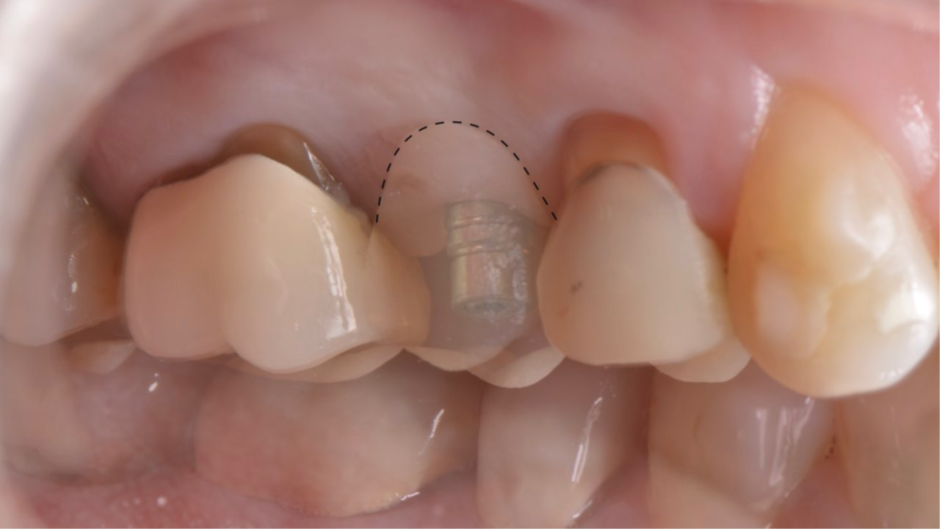

A coroa provisória foi fabricada por impressão 3D para criar os mesmos contornos da face vestibular dos dentes adjacentes (Figura 10). Uma coifa provisória de titânio foi parafusada ao pilar ideale para captura da coroa provisória impressa.

Nesse momento, existia uma grande diferença entre o contorno vestibular da coroa provisória e a posição da margem da mucosa (Figura 11). Então, foi utilizado uma resina flow para a captura da coroa provisória (Figura 12). E posteriormente, foi realizada o acabamento e polimento (Figura 13) para termos um excelente perfil de emergência da coroa (Figura 14).

Figura 10 – Coroa provisória fabricada por impressão 3D.

Figura 11 – Diferença entre o contorno vestibular da coroa provisória e a posição da margem da mucosa.

Figura 12 – Captura da coroa provisória com resina flow.